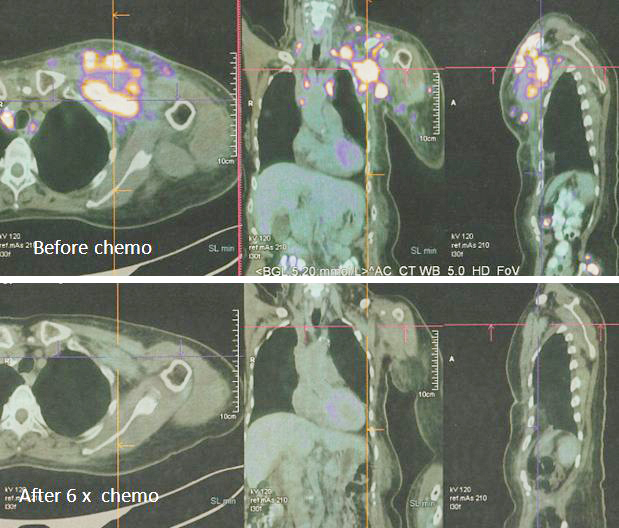

8. Pemindaian PET pada 14 April 2022 memang menunjukkan respon yang baik.

Sebelum kemo ———– setelah 6 siklus kemo

1. Temuan scan menunjukkan respon metabolik lengkap pada kekambuhan dinding dada, metastasis nodal dan penyebaran jauh.

2. Perubahan atelektasis baru pada dasar paru kiri dengan efusi pleura kiri ringan mungkin disebabkan oleh infeksi baru-baru ini.

Bandingkan ketiga gambar ini :

Kiri: Setelah operasi Lucy menjalani terapi alternatif, menolak kemoterapi. Hasilnya adalah metastasis luas (tengah).

Kanan: Lucy tidak punya pilihan selain menjalani kemoterapi. Hasil dari 6 siklus kemoterapi sungguh luar biasa! Selama lebih dari 25 tahun saya berurusan dengan pasien kanker, saya belum pernah melihat hasil kemoterapi yang luar biasa seperti ini. Salut dengan ahli onkologi! Anda menyelamatkan Lucy!

Faktanya, hasil chemo ini sangat sulit dipercaya sehingga orang tergoda untuk bertanya apakah itu asli dan bukan palsu? Jawaban saya TIDAK, studi detail hasil PET scan di bawah ini adalah nyata! Kaji gambar berikut dengan cermat – sebelum dan sesudah kemoterapi.